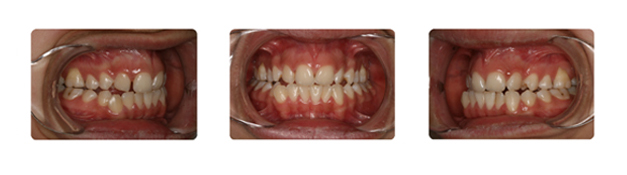

| بعد از قرارگیری دندانها در جای خود ومرتب شدن آنها فک نیز آماده جراحی میباشد: |

![]() |

| پس از جراحی فک وپایان درمان ارتدونسی دندانها و فک به نتیجه مطلوبی رسیده اند: |